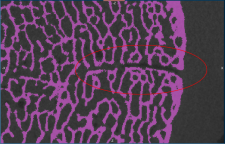

Closing the holes in an initial bone segmentation, including cortical pores and vascular canal inlets, and filling the inner areas of the segmentation, is the first step in the bone analysis workflow for accurately quantifying morphometric indices.

Cortical pore (circled)

and a filled region of interest in which the holes of the bone segmentation are closed.